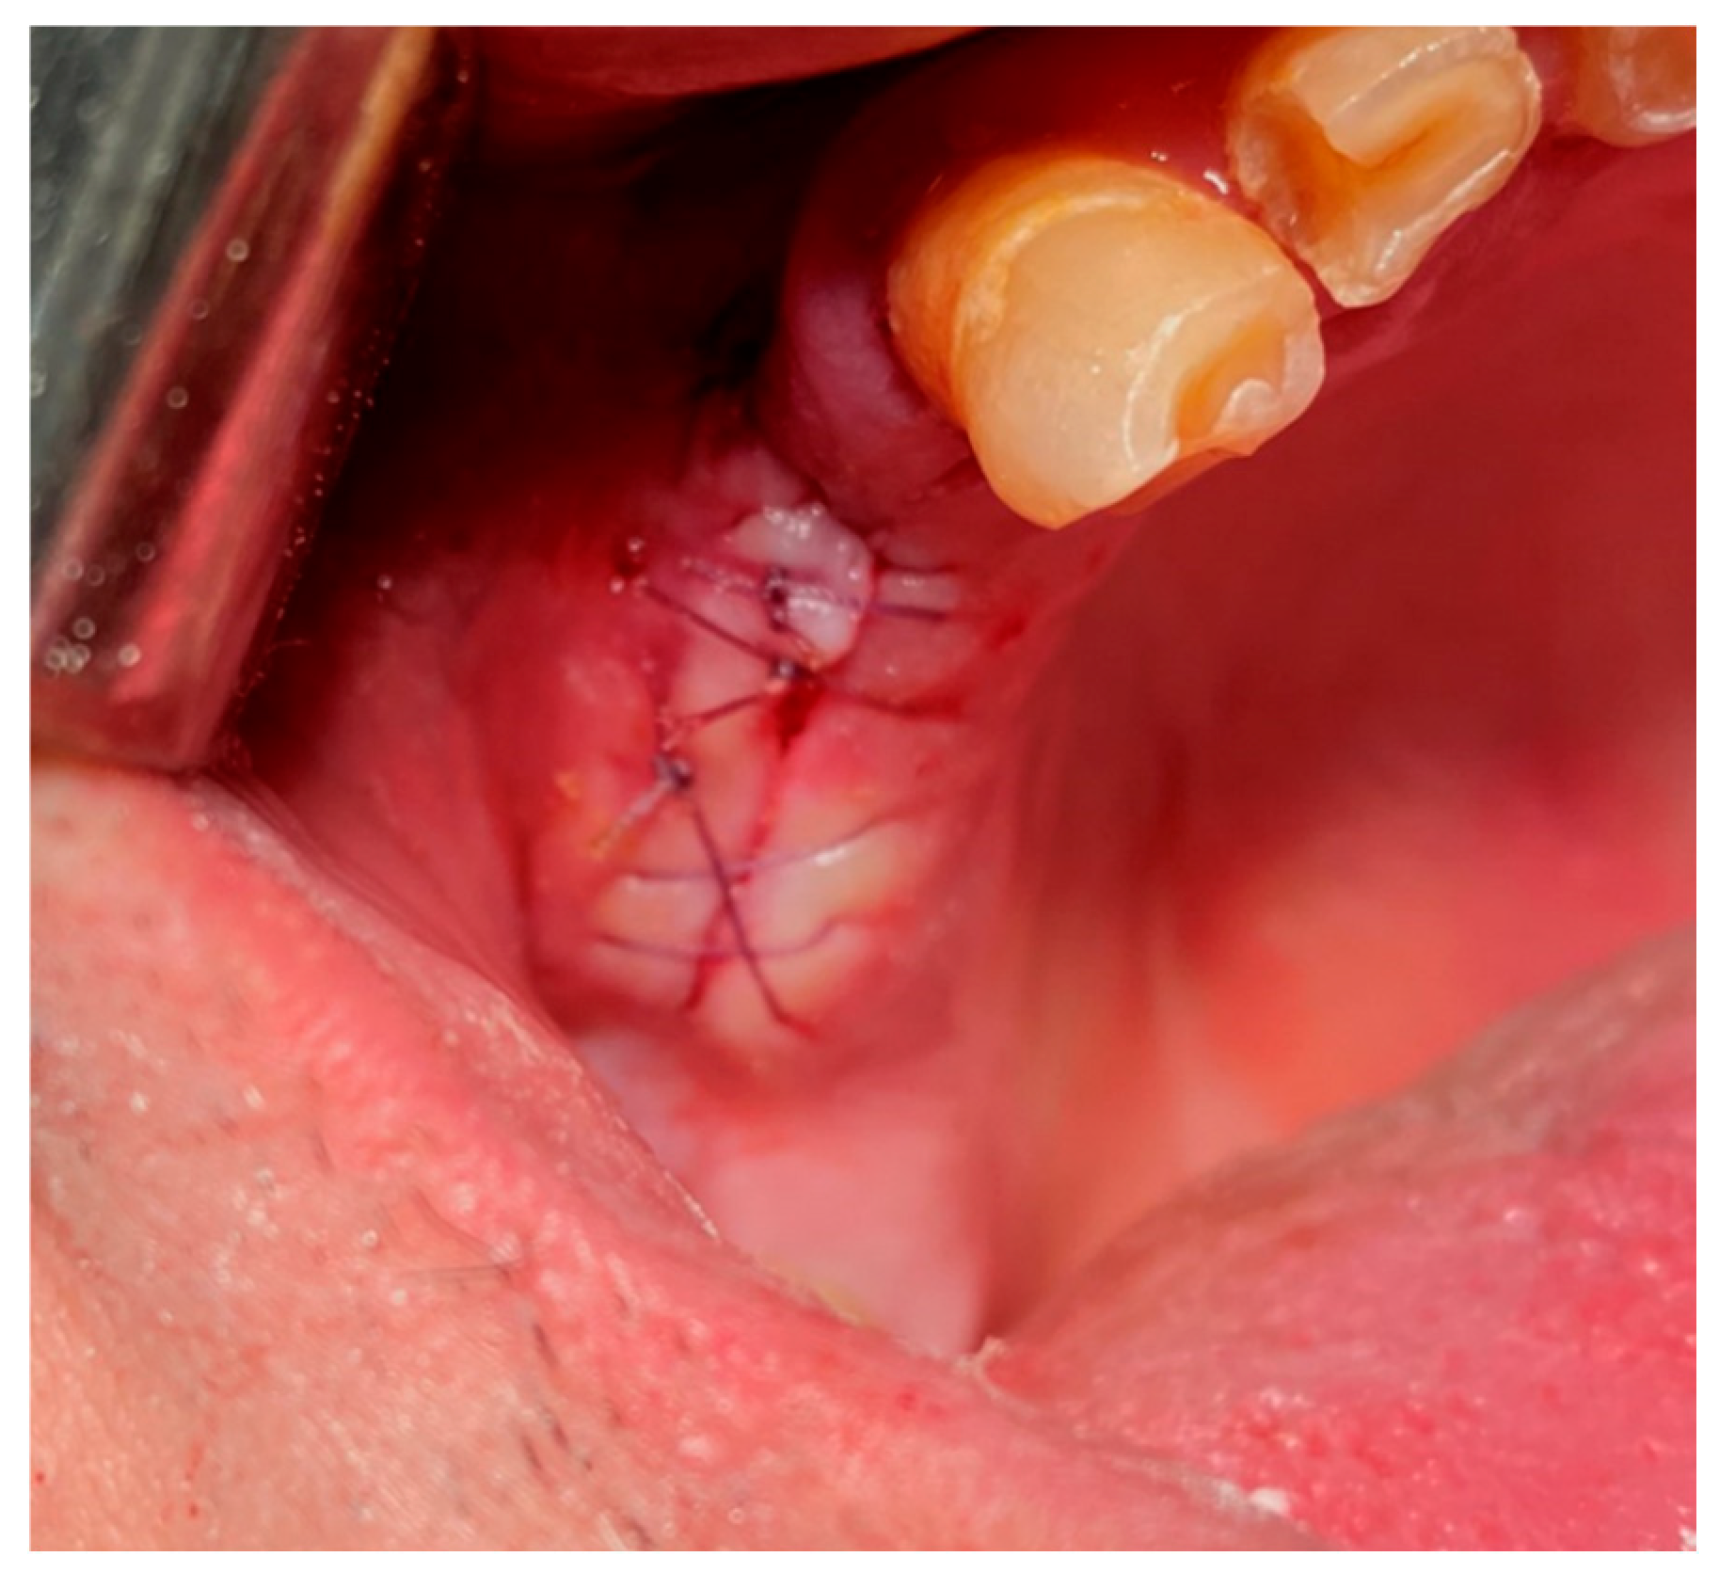

17. Surgical Suturing (Sutura Chirurgica)

- Single Throw Knot (One-Loop Knot, Figure 28)

- Square Knot (Simple Knot, Granny Knot, Figure 28):

- Surgeon's Knot (Two-Handed Knot, Double Throw Knot, Figure 28):